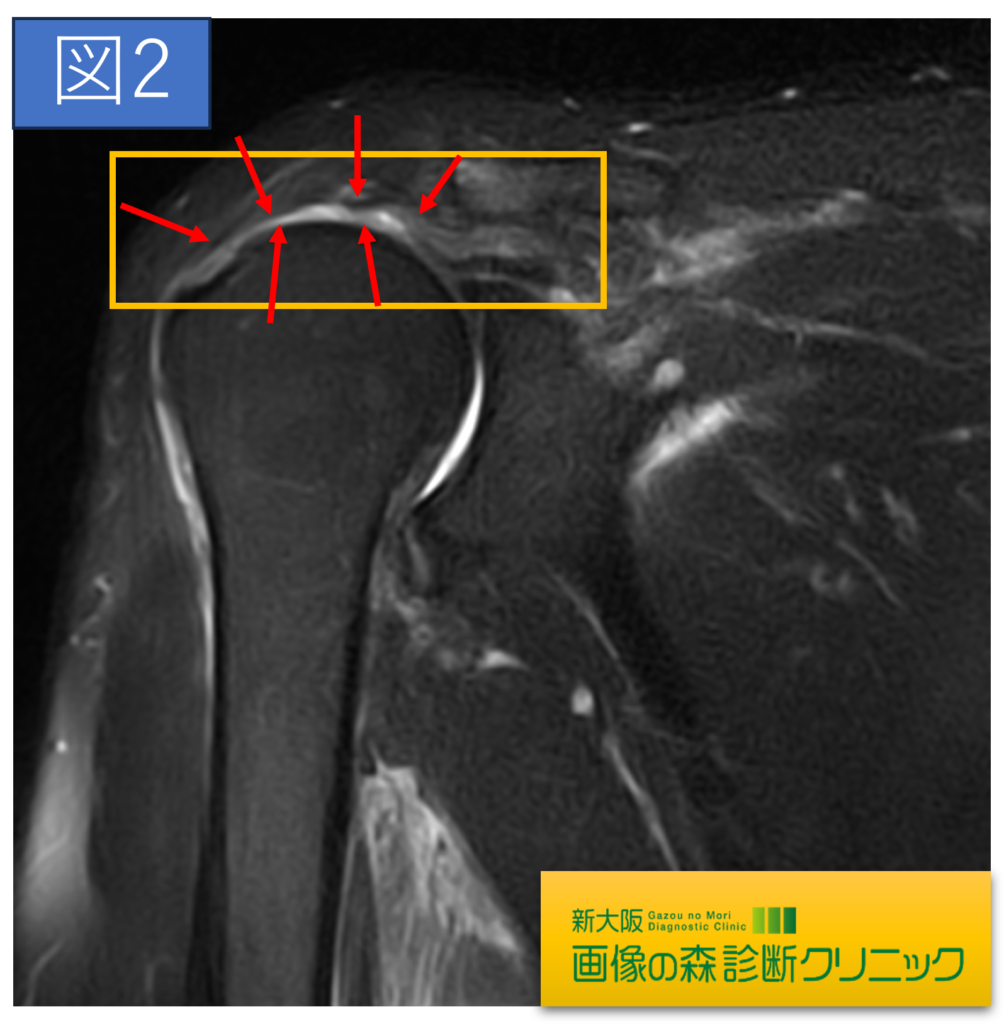

肩関節正常画像(冠状断像)

肩関節症例画像(冠状断像)

症例画像から図1~図4は棘上筋腱の画像です。□内に棘上筋腱の損傷を示します。正常では靱帯や腱は黒く描出されますが、損傷では白く高信号に描出されます。棘上筋腱損傷は、加齢による変性や転倒・スポーツ・仕事などによる外傷が原因となります。

症例画像から図1~図4は棘上筋腱の画像です。□内に棘上筋腱の損傷を示します。正常では靱帯や腱は黒く描出されますが、損傷では白く高信号に描出されます。棘上筋腱損傷は、加齢による変性や転倒・スポーツ・仕事などによる外傷が原因となります。